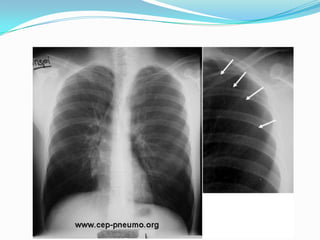

Pleurésie aigue:  Dlaigue d’instalation parfois brutale, latérothoracique augmentée par la toux, inspiration profonde et les changement de position. S’accompagne d’1 toux sèche, dyspnée si épanchement abondant.  Dg évoqué par examen clinique qui met en évidence une matité ou diminution voire abolition du murmure vésiculaire.  Radio pul: opacité déclive de limite supérieure concave en haut et en dedans.  Dg étiologique se fait par ponction exploratrice et évacuatrice.